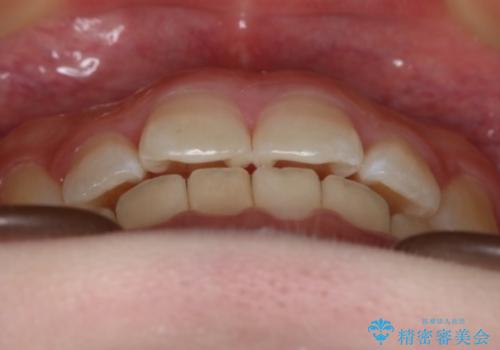

- 前歯のガタつきの改善を主訴に来院された患者様です。

ガタつきによる上顎正中の空隙や歯の突出感も気にされていました。